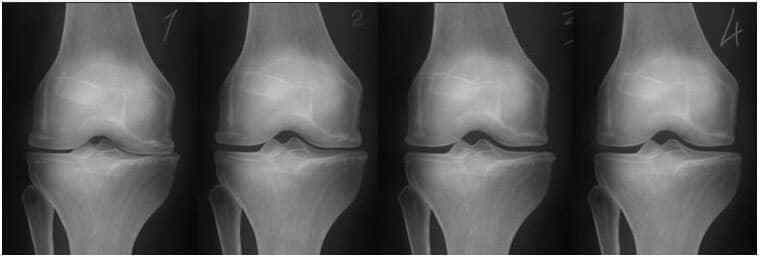

Суглоби

1. Недолік поживних речовин в суглобі. Хрящова тканина руйнується.

2. Відновлення хрящової тканини в суглобі через 2 тижні використання капсул Ortorion.

3. Відновлення хрящової тканини суглоба через 3 тижні застосування капсул Ortorion.

4. Здоровий суглоб після одного курсу капсул Ortorion.

На зображенні нижче показана типова картина відновлення колінного суглоба.